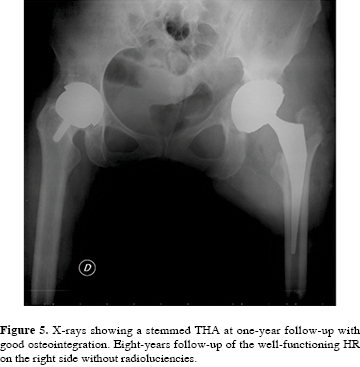

A 52-mm limb-length discrepancy was measured on anteroposterior preoperative radiographs (Figura 1).

Revision surgery was performed in June 2012 and a stemmed THA with modular dual mobility (MDM) system (ceramical 28-mm femoral head, 60-mm acetabular cup, metal insert and a 48-mm UHMWPE liner) (Stryker, Michigan, USA) was implanted. A good implant stability was achieved using autologous bone graft and two screws (Figura 5).

One year after revision surgery, the patient is doing well; hip pain has disappeared on the left side (HHS 95), while the right one has still an excellent clinical outcome (HHS 98), with radiographs showing a complete osteointegration of the implant.